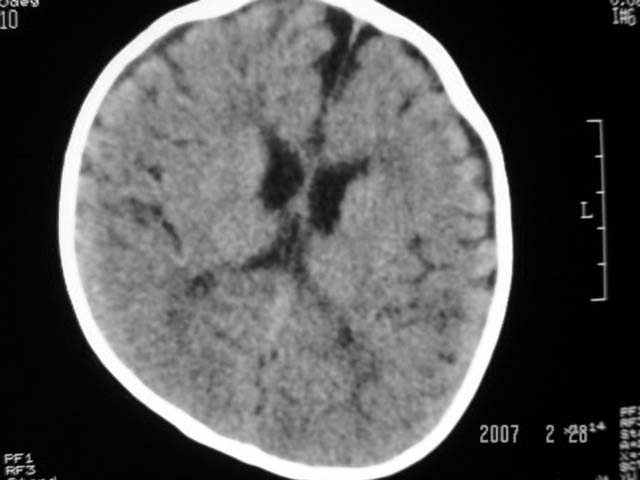

标题: PED0015:男,8M,发现不会坐立及神情异常,前囟已闭,双眼斜视,

脑回较深,白质范围小,灰白质比例失调。余未见明显异常。

考虑:脑白质发育不良,必要时请做mri进一步检查。